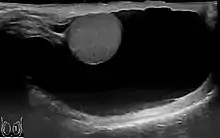

Communicating hydrocele testis, caused by the failure of the processus vaginalis closure.

During embryogenesis, the testis descends through the inguinal canal, drawing a diverticulum of peritoneum into the scrotum as it descends. This peritoneal tissue is known as the processus vaginalis. Normally, the communication between the processus vaginalis and the peritoneum is obliterated, and the tunica vaginalis is the tissue that remains overlying the testis and the epididymis. Congenital hydrocele testis results when the processus vaginalis remains, allowing fluid from the peritoneum to accumulate in the scrotum.